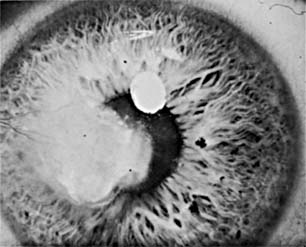

The typical corneal ulcer associated with avitaminosis A is centrally located and bilateral, gray and indolent, with a definite lack of corneal luster in the surrounding area (Figure 6-10). The cornea becomes soft and necrotic (hence the term, "keratomalacia"), and perforation is common. The epithelium of the conjunctiva is keratinized, as evidenced by the presence of a Bitot spot. This is a foamy, wedge-shaped area in the conjunctiva, usually on the temporal side, with the base of the wedge at the limbus and the apex extending toward the lateral canthus. Within the triangle the conjunctiva is furrowed concentrically with the limbus, and dry flaky material can be seen falling from the area into the inferior cul-de-sac. A stained conjunctival scraping from a Bitot spot will show many saprophytic xerosis bacilli (Corynebacterium xerosis; small curved rods) and keratinized epithelial cells.

Figure 6-10

Figure 6-10: Keratomalacia with ulceration associated with xerophthalmia (dietary) in an infant. (Photo by Diane Beeston.)